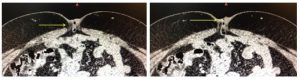

Con la sospecha preoperatoria de hernia umbilical estrangulada con asa intestinal fistulizada, se decide conducta quirúrgica. Se realiza incisión en rombo (incluyendo ombligo) transversal, destacando anillo herniario de 15 mm. Apertura de saco herniario, en cuyo fondo se identifica un divertículo de Meckel de 6 cm de largo y 2 cm de diámetro aproximadamente, perforado en sector distal y fistulizado a ombligo (ver imágenes 3 y 4). Exteriorización de tramo de asas de intestino delgado. Se realiza diverticulectomía con máquina de sutura lineal cortante (carga azul, número 75) en base diverticular, extracción de pieza y envío a anatomía patológica. Invaginación de grapas con sutura de poligalactina 910 de 4/0. Reintroducción de asas a cavidad abdominal, no se objetiva contaminación en la misma. Herniorrafia con polipropileno del 1, con puntos separados. Cierre de piel con nylon 3/0.

Imágenes 3 y 4. Se visualiza divertículo de Meckel de base amplia (flecha azul) y en su sector distal trayecto fistuloso a piel (circulo amarillo). Protruyendo por orificio herniario asa intestinal (flecha negra).